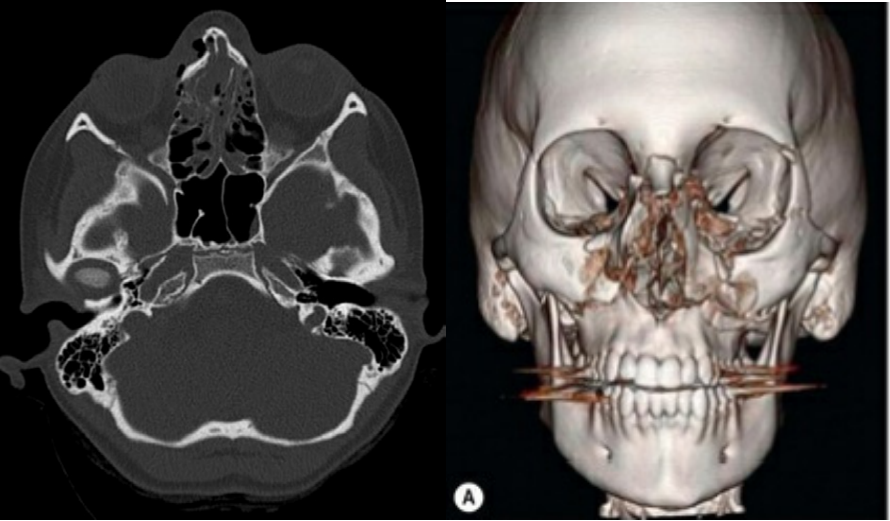

O exame padrão-ouro para o diagnóstico é a Tomografia Computadorizada (TC) de face com reconstrução 3D, que oferece uma visualização detalhada das estruturas ósseas nos planos axial, coronal e sagital.

- Fratura de Maxila (Classificação de Le Fort): São fraturas de alto impacto que seguem padrões previsíveis, classicamente descritos por René Le Fort.

- Le Fort II: Fratura piramidal que se estende da região pterigoide, através do assoalho da órbita, até a raiz do nariz.

- Le Fort III: Conhecida como disjunção craniofacial, representa uma separação completa entre os ossos da face e a base do crânio. Resulta em alongamento e retração da face. As fraturas Le Fort II e III podem estar associadas a fístula liquórica.